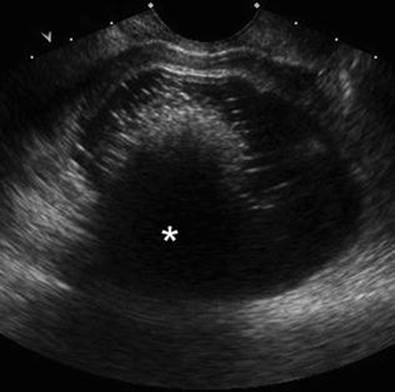

Fig. 4.6

Ovarian teratoma on transvaginal ultrasound. The cystic adnexal mass has a central dense echogenic nodule (the Rokitansky nodule) causing posterior acoustic shadowing (*). The Rokitansky nodule is composed of the fat, bone, and hair (Reprinted from Heilbrun et al. [3], with permission)